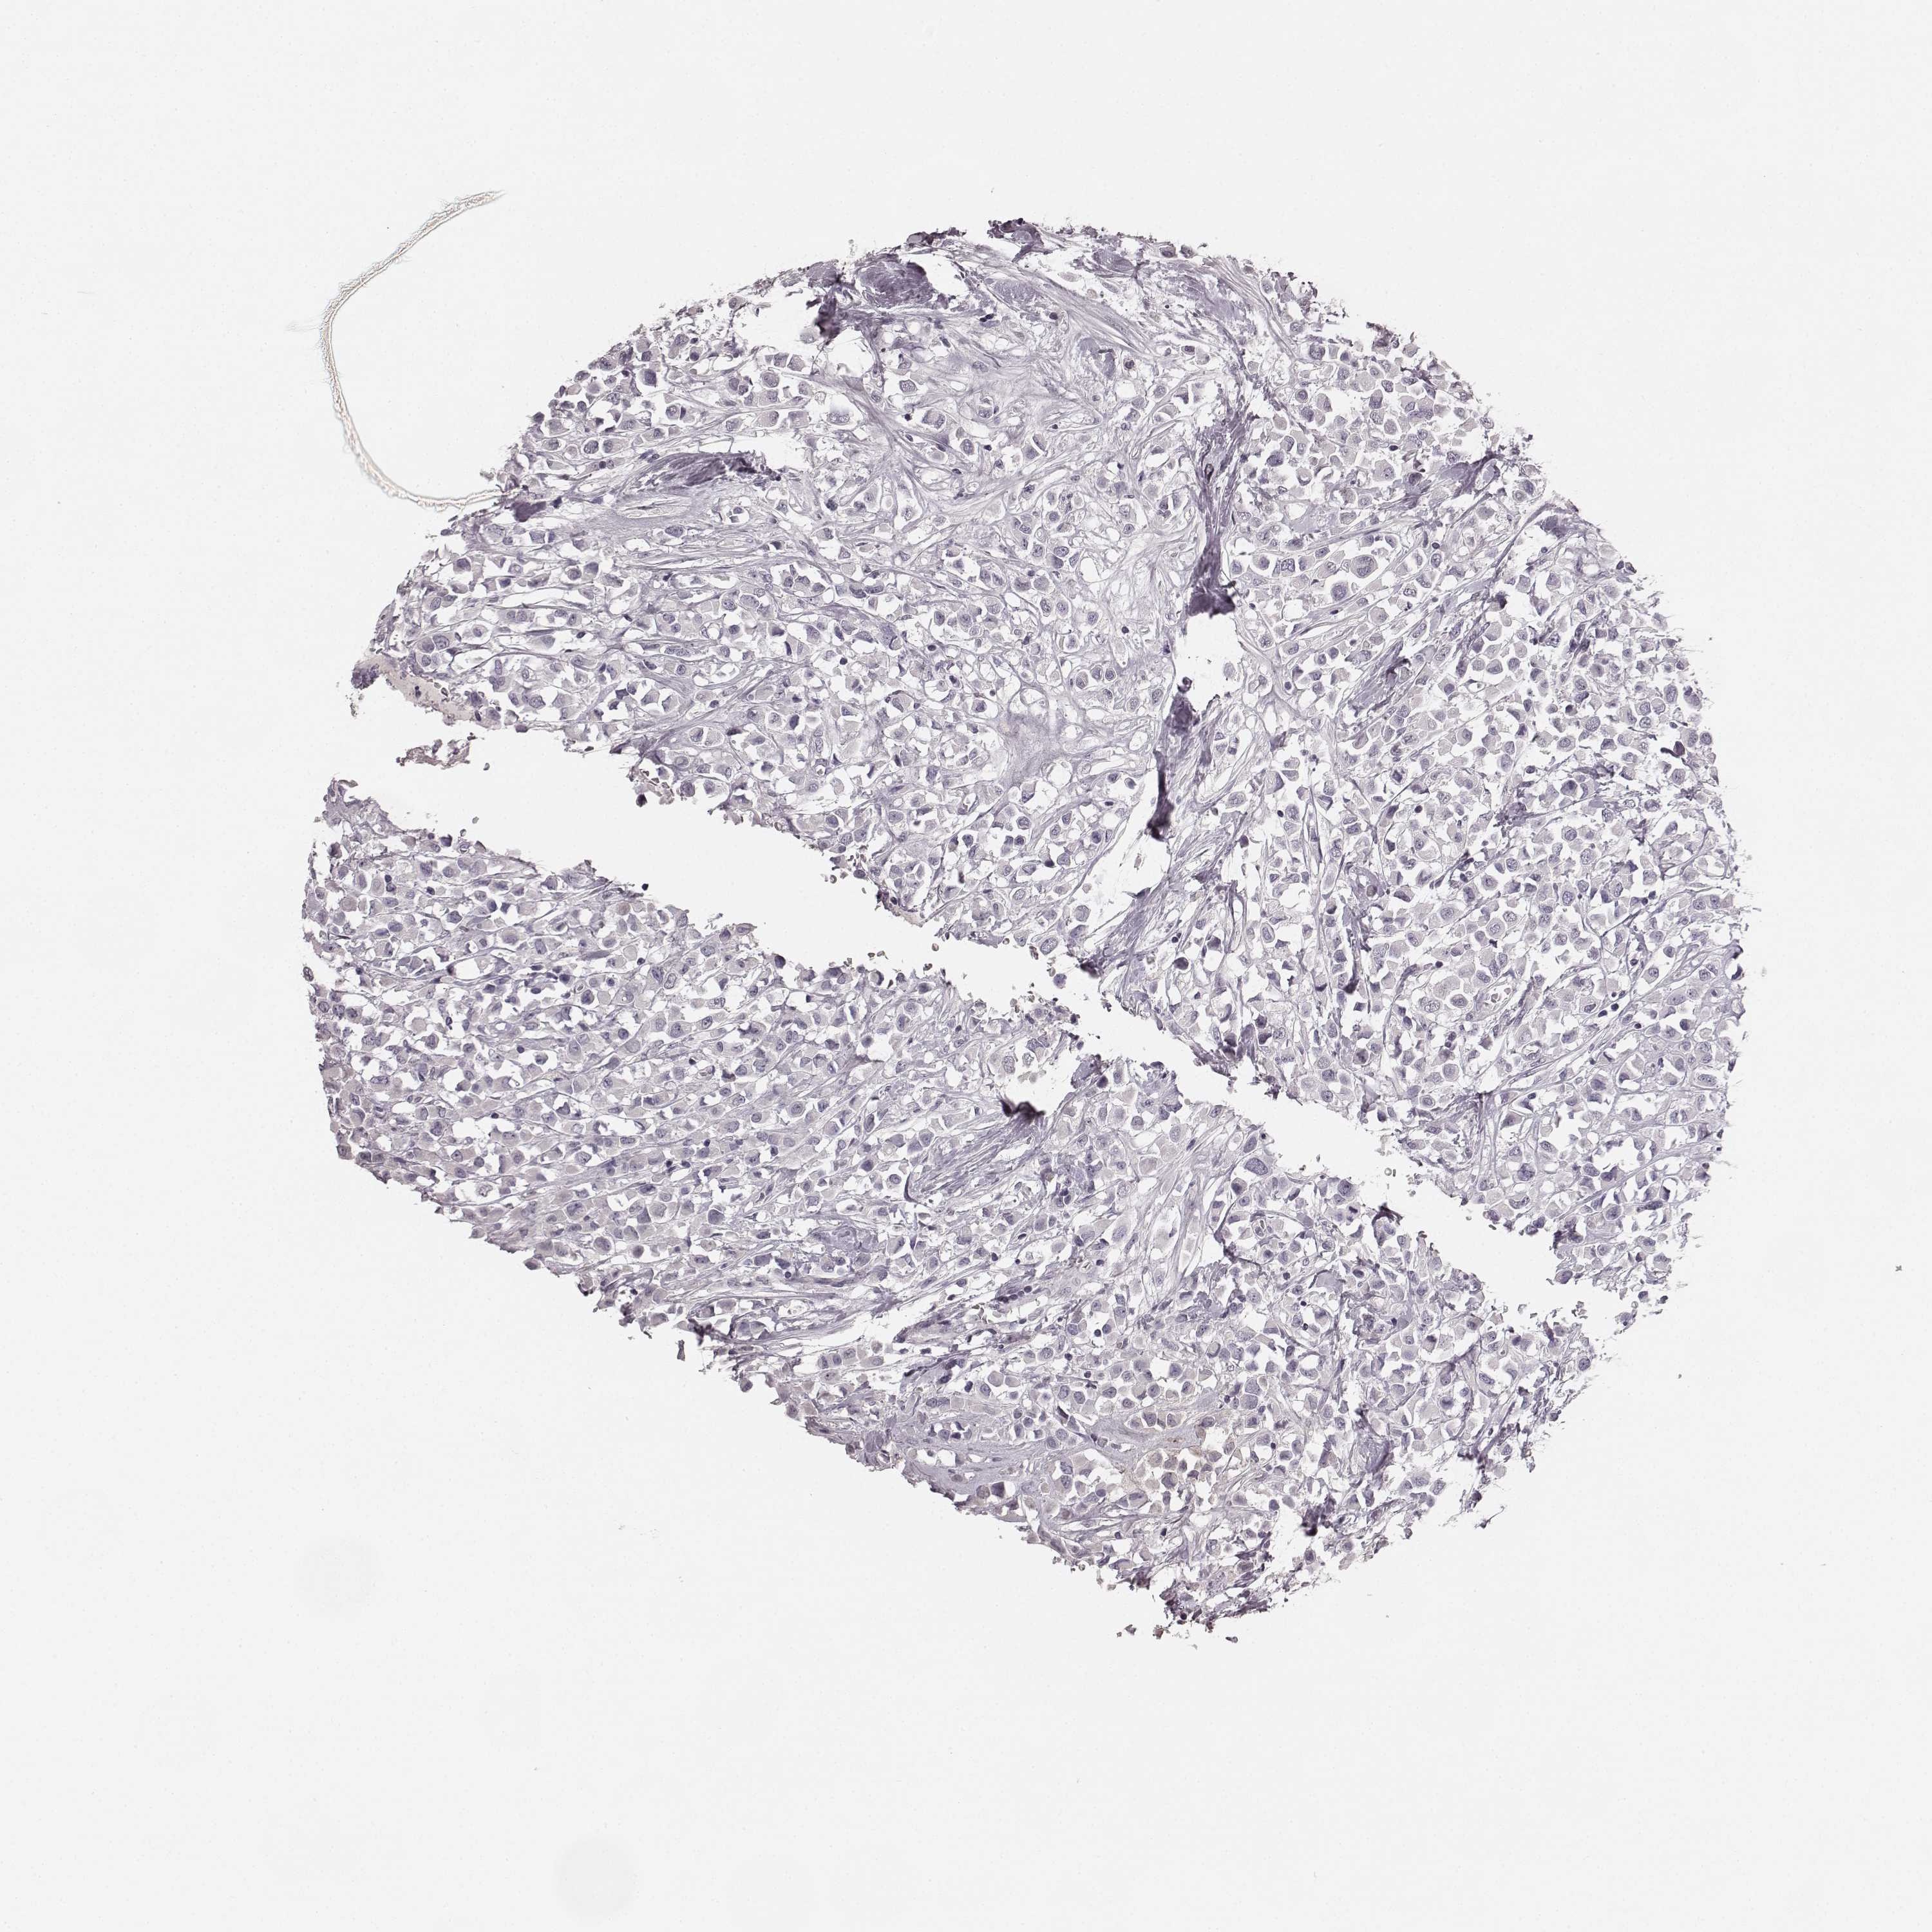

CANCER BREAST CANCER Show tissue menu

BRCA TCGA BRCA VALIDATION PROTEIN EXPRESSION